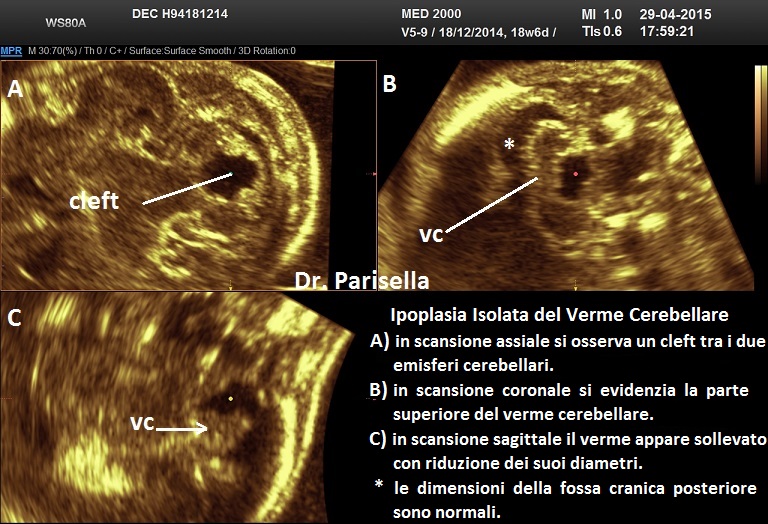

Ipoplasia Isolata del Verme Cerebellare

Si parla di ipoplasia isolata del verme cerebellare quando il verme è piccolo (interamente o in parte) e non vi sono altre alterazioni delle strutture della fossa cranica posteriore. La diagnosi ecografica si basa su: presenza, in scansione assiale, di cleft tra i due emisferi cerebellari; in scansione longitudinale il verme appare piccolo e sollevato; nelle forme parziali si osserva, in scansione coronale, la normale presenza della porzione superiore del verme; la fossa cranica posteriore appare di dimensioni normali.

Il rischio di aneuploidie e sindromico è elevato.